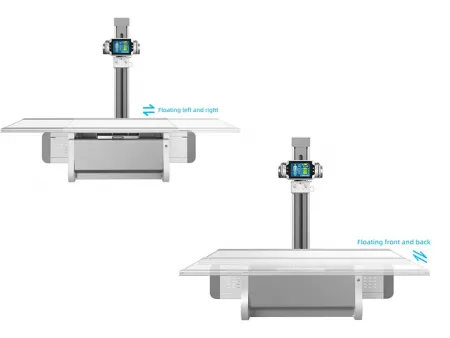

| Mesa de fotografía | |

| Tipo | Mesa de radiografía |

| Tamaño de la mesa | 2100×800 mm X65 mm |

| Soporte de carga | 300 KG |

| Parte delantera y trasera flotante | 150 mm / 150 mm |

| Parte derecha e izquierda flotante | 400 mm / 400 mm |

Sólida y funcional, esta mesa está diseñada para soportar hasta 300 kg, ofreciendo comodidad al paciente y una operación sencilla para el profesional.